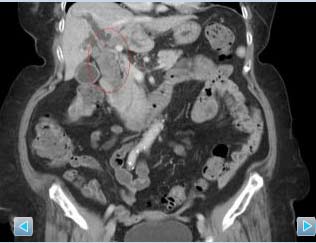

外科主任黄铭德表示,老太太体内的66颗胆道结石,将本来直径只有0.6至0.8cm的胆道撑到2.5cm宽,在体内几乎要爆裂,加上老太太年事已高,两年中好几次呕吐、腹痛、昏迷送医急救,因为不敢开刀拖延至今。

黄铭德指出,年事较高对于开刀须全身麻醉有所顾忌,可能对患者心脏或血管造成压力,产生某些后遗症,现在可改用内视镜的方式,如若结石数量太多或结石太大,可利用内视镜在腹部利用3至4个1公分的伤口将胆石从胆管取出,位于肝内的胆管也可施行切肝手术,术后维持饮食清淡即可。若结石数量不多,则可经由12指肠以内视镜取出结石。